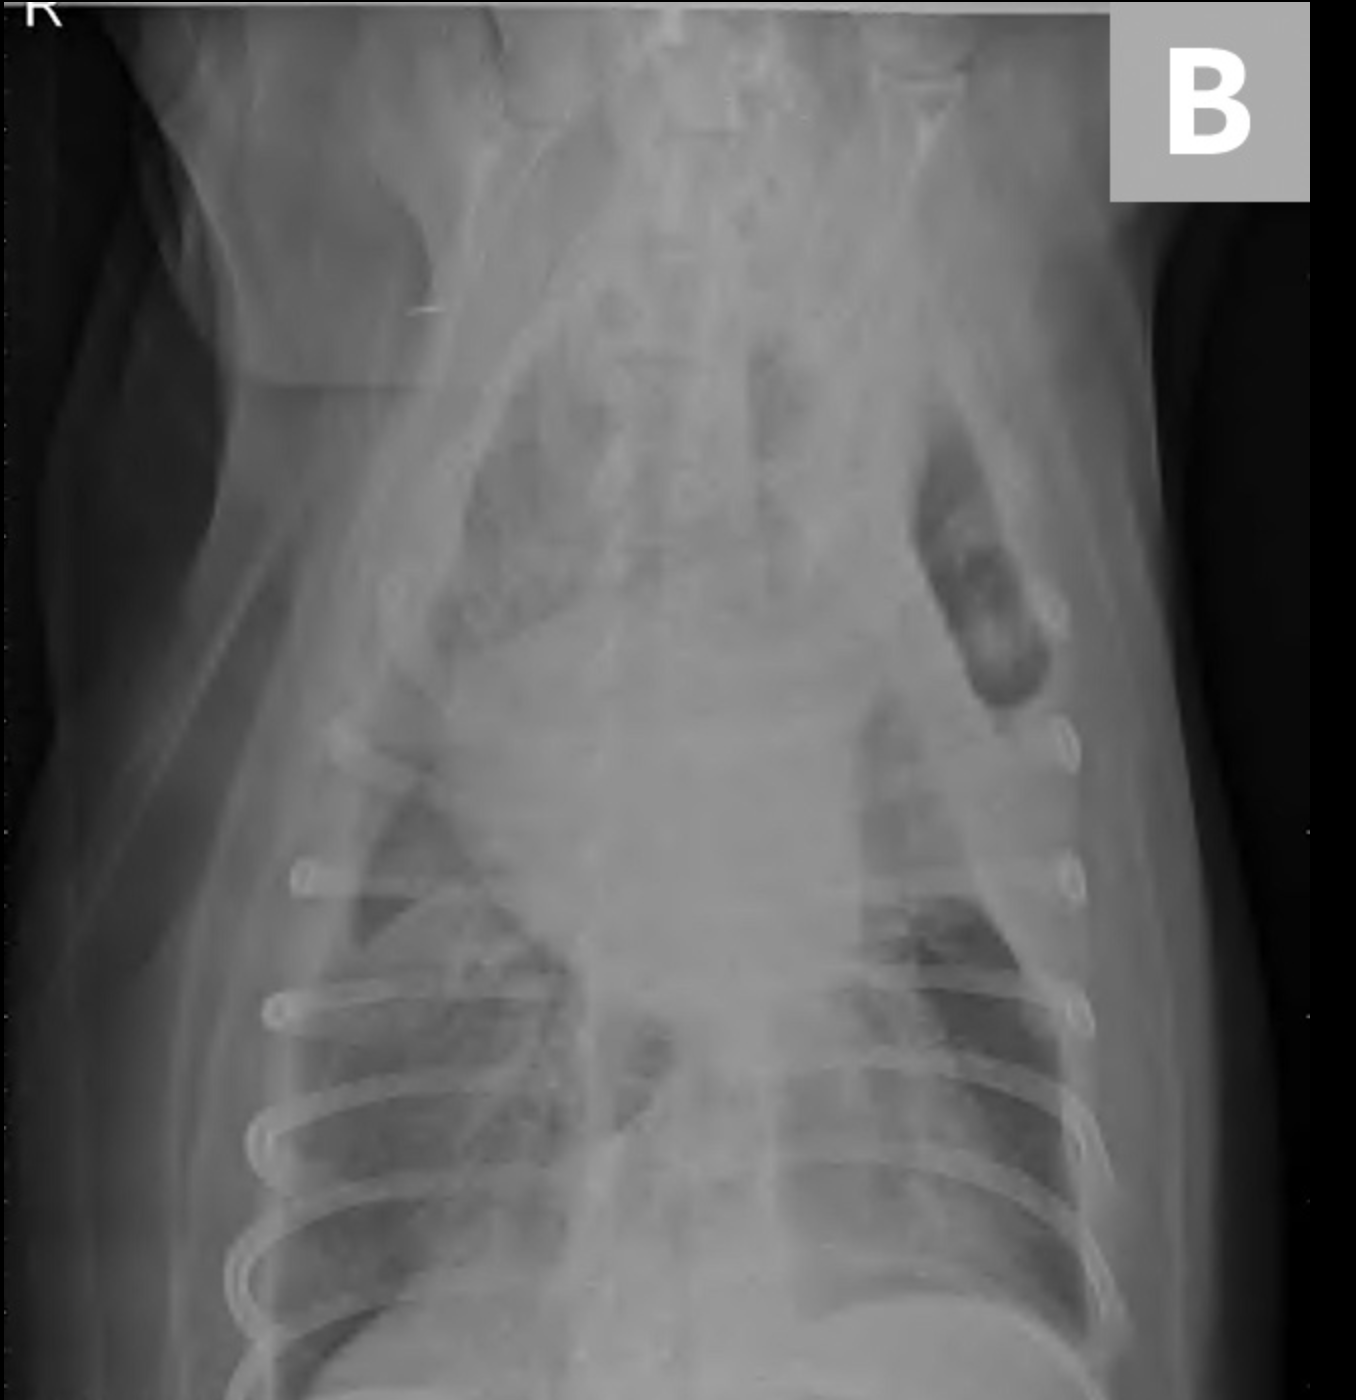

Las radiografías torácicas laterales derechas revelaron una gran cantidad de opacidad de líquido / tejido blando que oscurece la silueta cardíaca. Las radiografías ventrodorsales mostraron un aumento de la opacidad de los tejidos blandos en el hemitórax izquierdo, principalmente en los campos del pulmón craneal y medio. En el hemitórax izquierdo se observó un patrón intersticial leve, una línea de fisura pleural y borramiento del borde en el corazón (Figura 1).

Los hallazgos radiográficos sugirieron una combinación de enfermedad pulmonar y del espacio pleural. Los diagnósticos diferenciales incluyeron derrame pleural (p. Ej., Hemotórax, piotórax, quilotórax, hidrotórax, neoplasia) y la masa del espacio pleural o efecto de masa (p. Ej., Neoplasia, consolidación o torsión del lóbulo pulmonar, absceso / granuloma).